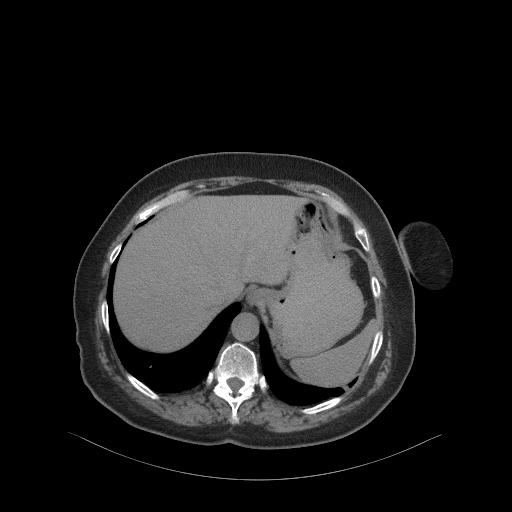

Generated VENOUS CT scan (A→B translation)

Full window (WL 1023.5, WW 4095 β†’ Low βˆ’1024, High +3071)

Actual HU range: [-1024.0, 1032.9]